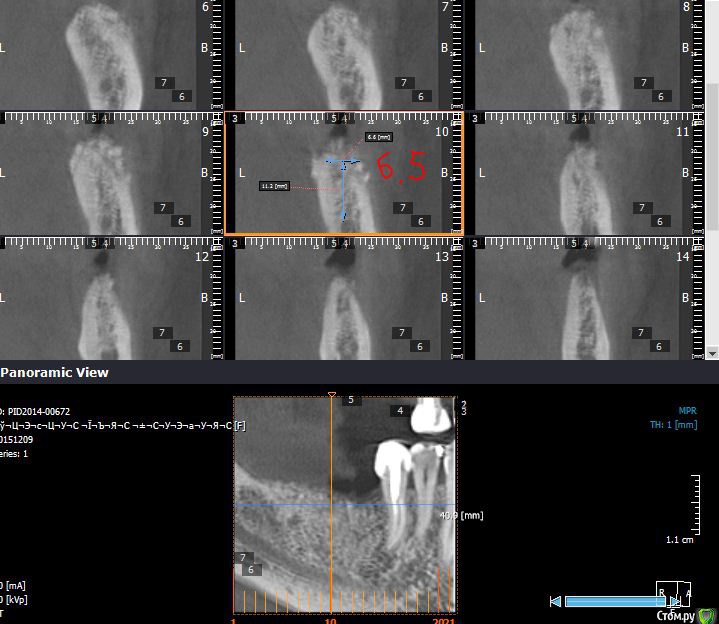

Endorphin Опубликовано 1 февраля, 2016 Автор Поделиться Опубликовано 1 февраля, 2016 Если возможно, то выкладывайте, пожалуйста КТ с измерениями в миллиметрах. А то совсем не понятно что там и как выросло. До аугментации. При такой форме не решился расщеплять. От вершины гребня до нерва не многим более 11 мм в среднем на протяжении дефекта. Ширина там, где хотелось бы видеть платформу 2-3мм. 5 месяцев после аугментации. Видно что частично графт скорее всего уйдет, так и вышло. Ширина 6.5мм, высота 12-13. немного не там где хотелось, но имплантация возможна. Контрольная кт после установки имплантатов. Dentium sl 3.8x10 3 Ссылка на комментарий